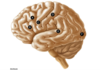

Broca’s Aphasia

- What happens to speech?

- What happens to comprehension?

- Where does the lesion occur?

- Speech is nonfluent

- Comprehension is intact

- B - Inferior Frontal Gyrus

“broken boca”

boca = mouth in spanish

Wernicke’s Aphasia

- What happens to speech?

- What happens to comprehension?

- Where does the lesion occur?

- Speech is fluent but lacks meaning

- Comprehension is impaired

- E - Superior Temporal Gyrus

“Wernicke is wordy but makes no sense”

Conduction Aphasia

- What happens to speech?

- What happens to comprehension?

- Where does the lesion occur?

- What happens to repetition?

- Speech is fluent

- Comprehension is intact

- Arcuate FasCiculus

- Lack repetition

(they cannot repeat a sentence after hearing it)